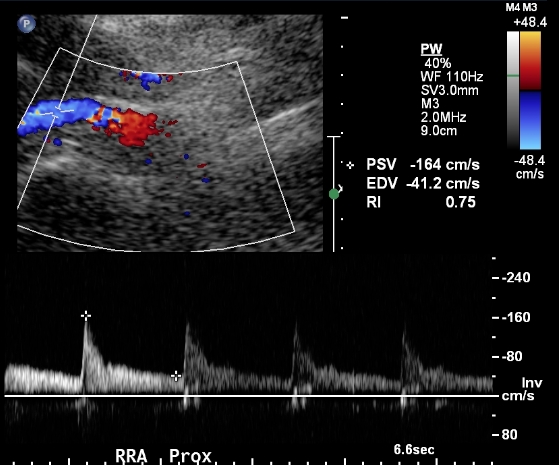

The next step is to identify the renal arteries. Each renal artery should be sampled in its origin and proximal, mid and distal portions. The distal portion of the renal artery is often difficult to obtain from the midline even in easy renal artery ultrasound. The proximal portion is difficult to obtain from the flank and therefore effort should be made to obtain it from the midline.

Sampling from the renal artery should be performed with angle correction.

A high-quality renal artery ultrasound will repeat similar measurements from both the midline and the flank approach. If there is great discrepancy between these measurements, it may mean that one of them is wrong.